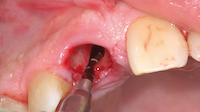

photo n°3 :

Détermination de la hauteur de la corticale vestibulaire et du diamètre de l’alvéole à l’aide d’une sonde boule graduée.

photo n°4 :

Détermination du futur axe d’insertion de l’implant en prenant appui au niveau de la paroi palatine.